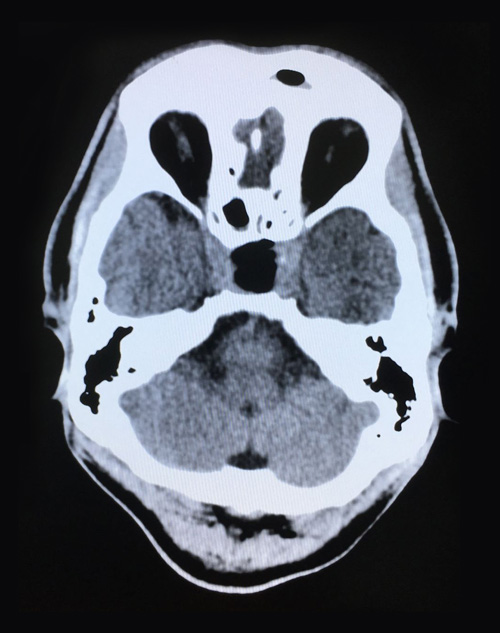

術(shù)后第二天影像:腫瘤切除干凈,鞍內(nèi)腦脊液填充

整個(gè)切除手術(shù)用時(shí)1小時(shí)左右,術(shù)中出血量很少,腫瘤切除干凈;颊咔逍押,被安全送到ICU(重癥監(jiān)護(hù)室)監(jiān)護(hù)。經(jīng)鼻蝶竇入路垂體瘤切除微創(chuàng)手術(shù)具有腫瘤暴露佳,創(chuàng)傷和危險(xiǎn)性小,手術(shù)時(shí)間短、顱面外觀(guān)無(wú)損傷,手術(shù)效果好等優(yōu)點(diǎn),但該手術(shù)方式對(duì)專(zhuān)家的技術(shù)水平也有著非常高的要求。